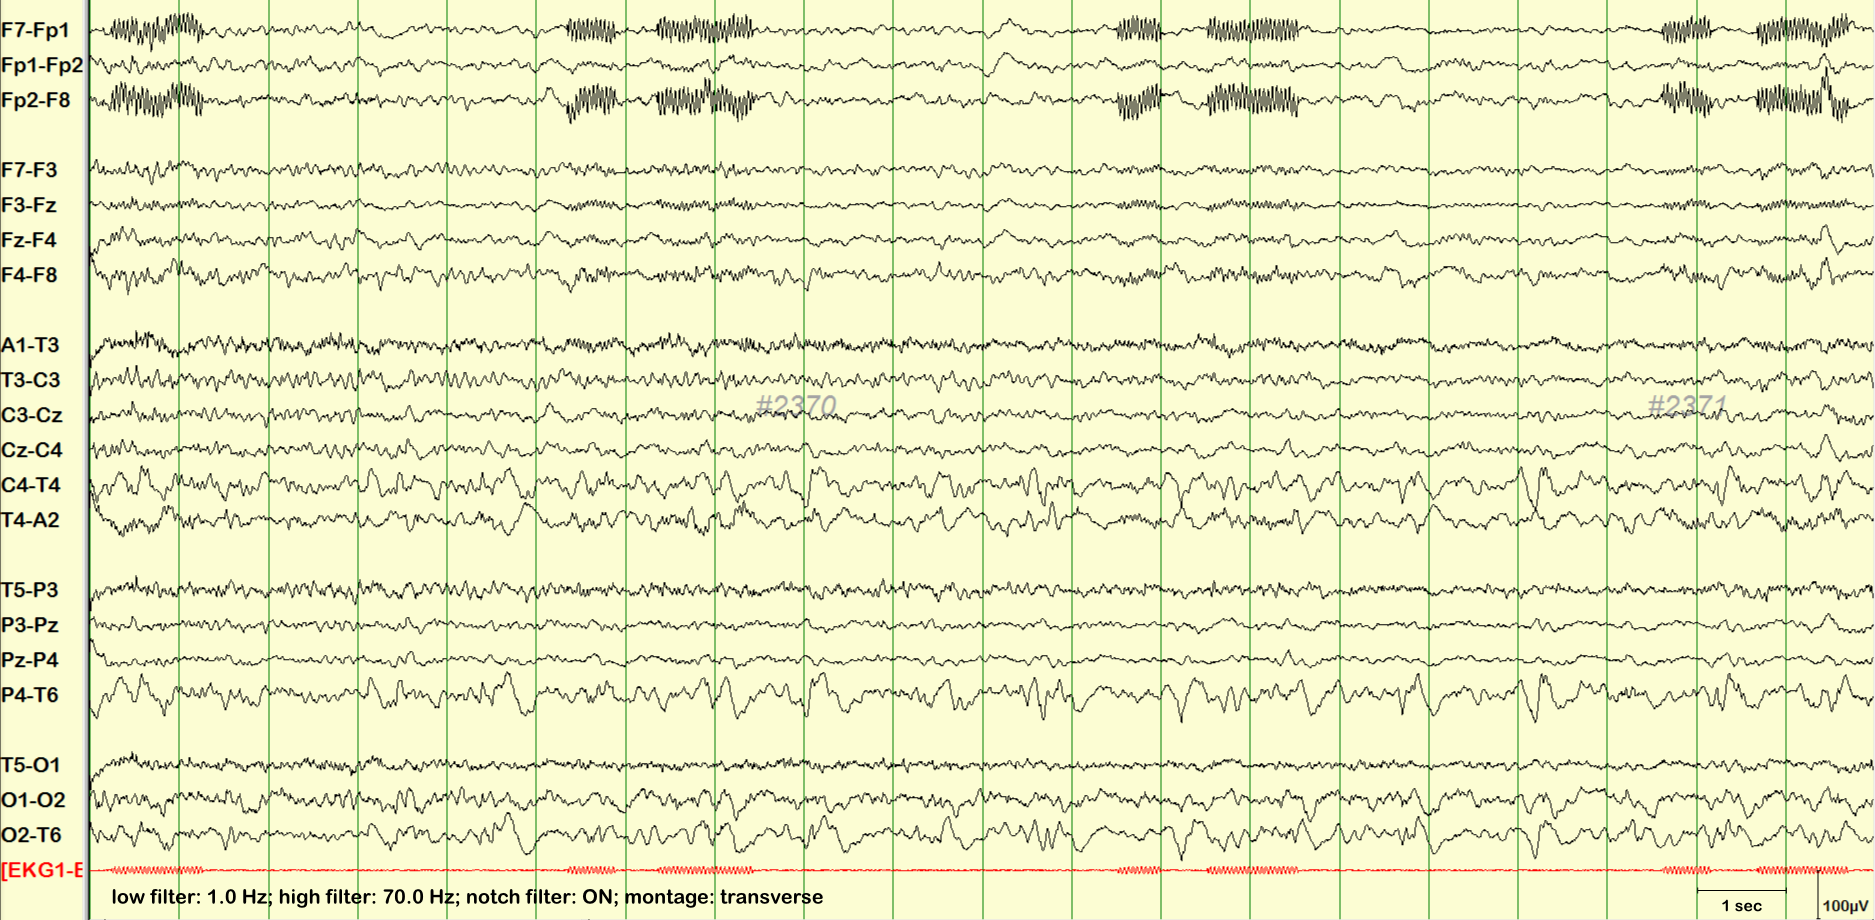

telephone artifact

telephone